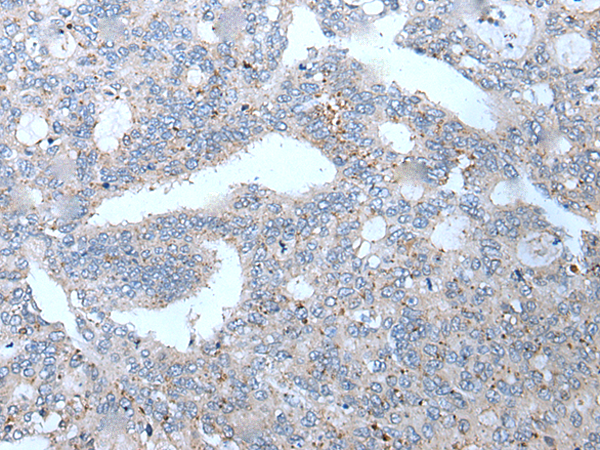

分类: 科研抗体货号: P05998别名: PYM; WIBG应用: IHC反应种属: Human, Mouse